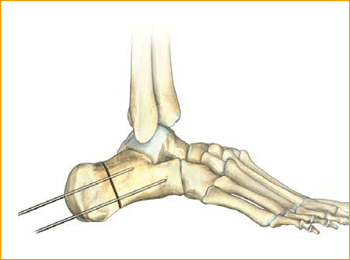

4. GUIDE WIRE PLACEMENT

The body of the calcaneus is displaced medially or laterally and held in place with two guide pins. The distal portion of the pins are placed at the volar aspect of the angle of Gissane in order to capture solid bone distally and assist with compression of the osteotomy by the screws.

Confirm guide pin placement under fluoroscopy.

Tip: The soft tissue protector and arthroscopic probe can be used to assist in guide wire placement.